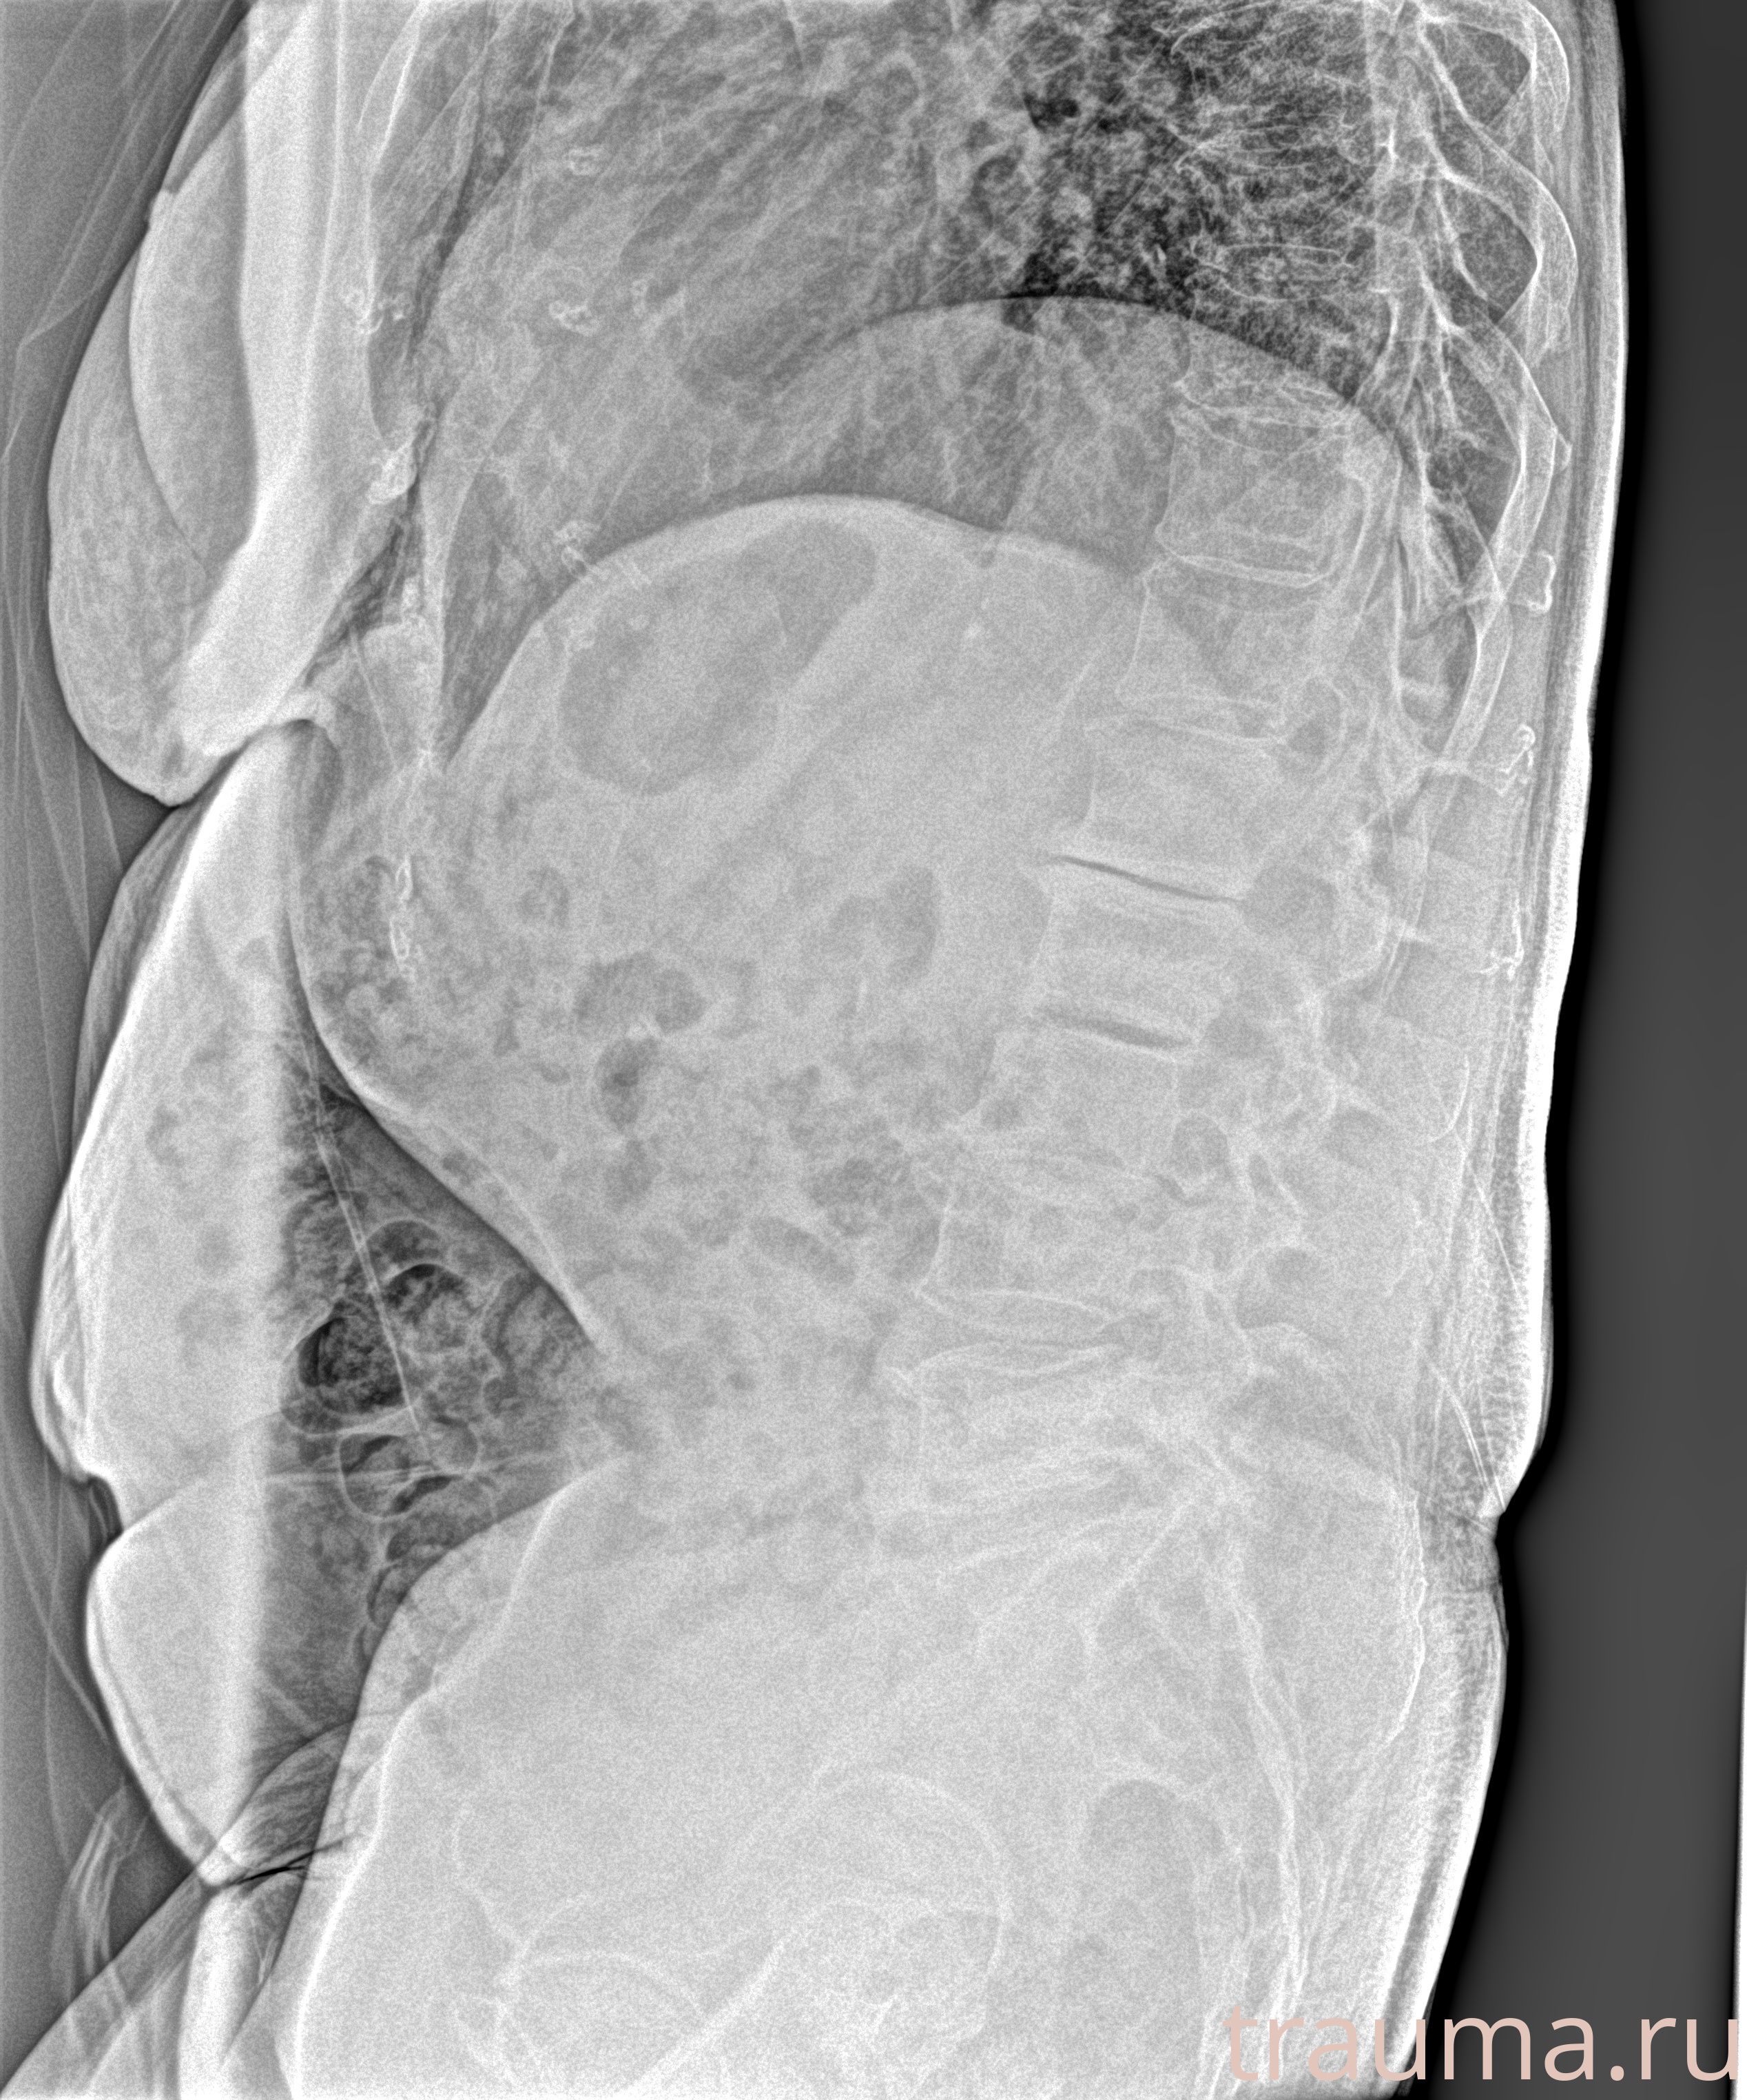

Рентген на дому: по вашему адресу приезжает врач-рентгенолог, травматолог-ортопед с мобильным рентгеновским аппаратом, проводит диагностику травмы или заболевания, делает необходимые рентгенограммы, дает рекомендации по дальнейшему лечению. Получить качественные снимки в домашних условиях возможно благодаря уникальной методике, разработанной МосРентген Центром для института  Склифосовского